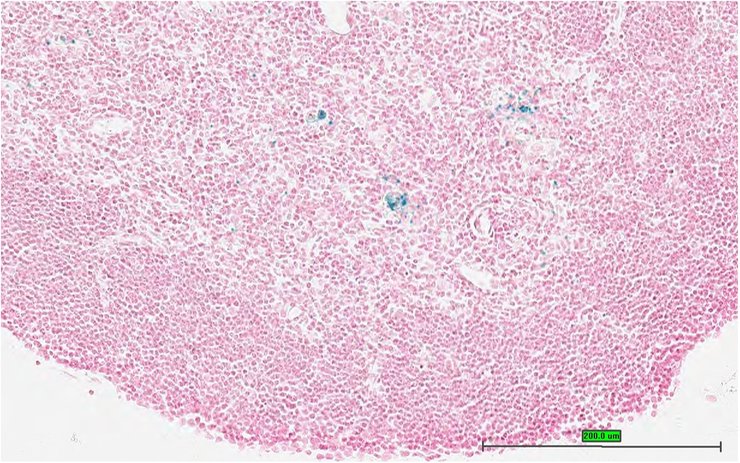

Specimen UC Davis_1866044: postnatal adult; Peli1tm1b(EUCOMM)Wtsi/Peli1+ (more )

Structure Level Pattern Image Note

TS28: thymus Present UC Davis_1866044